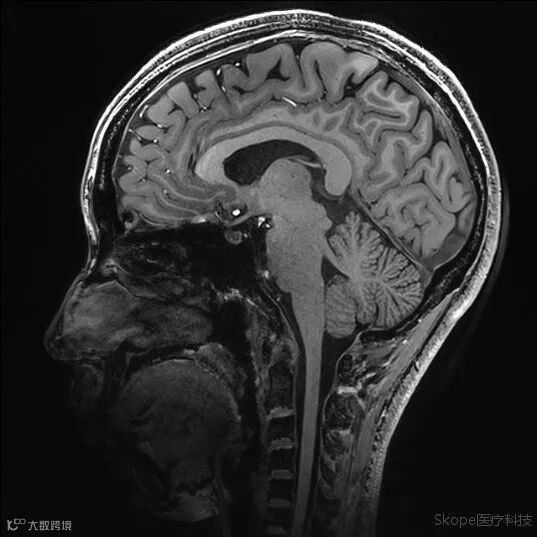

Sagittal T2 TSE

pTx有效改善了小脑区域图像均匀性。

Right brain hemisphere

Left brain hemisphere